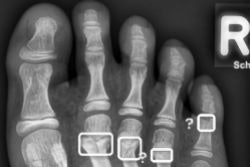

The U.K. Royal College of Radiologists (RCR) has released a guidance document on pediatric trauma radiology that is available for free download.

The document is intended to support decision-making between clinicians and radiologists about imaging pediatric patients with major trauma and covers blunt trauma, penetrating trauma, and blast injury.